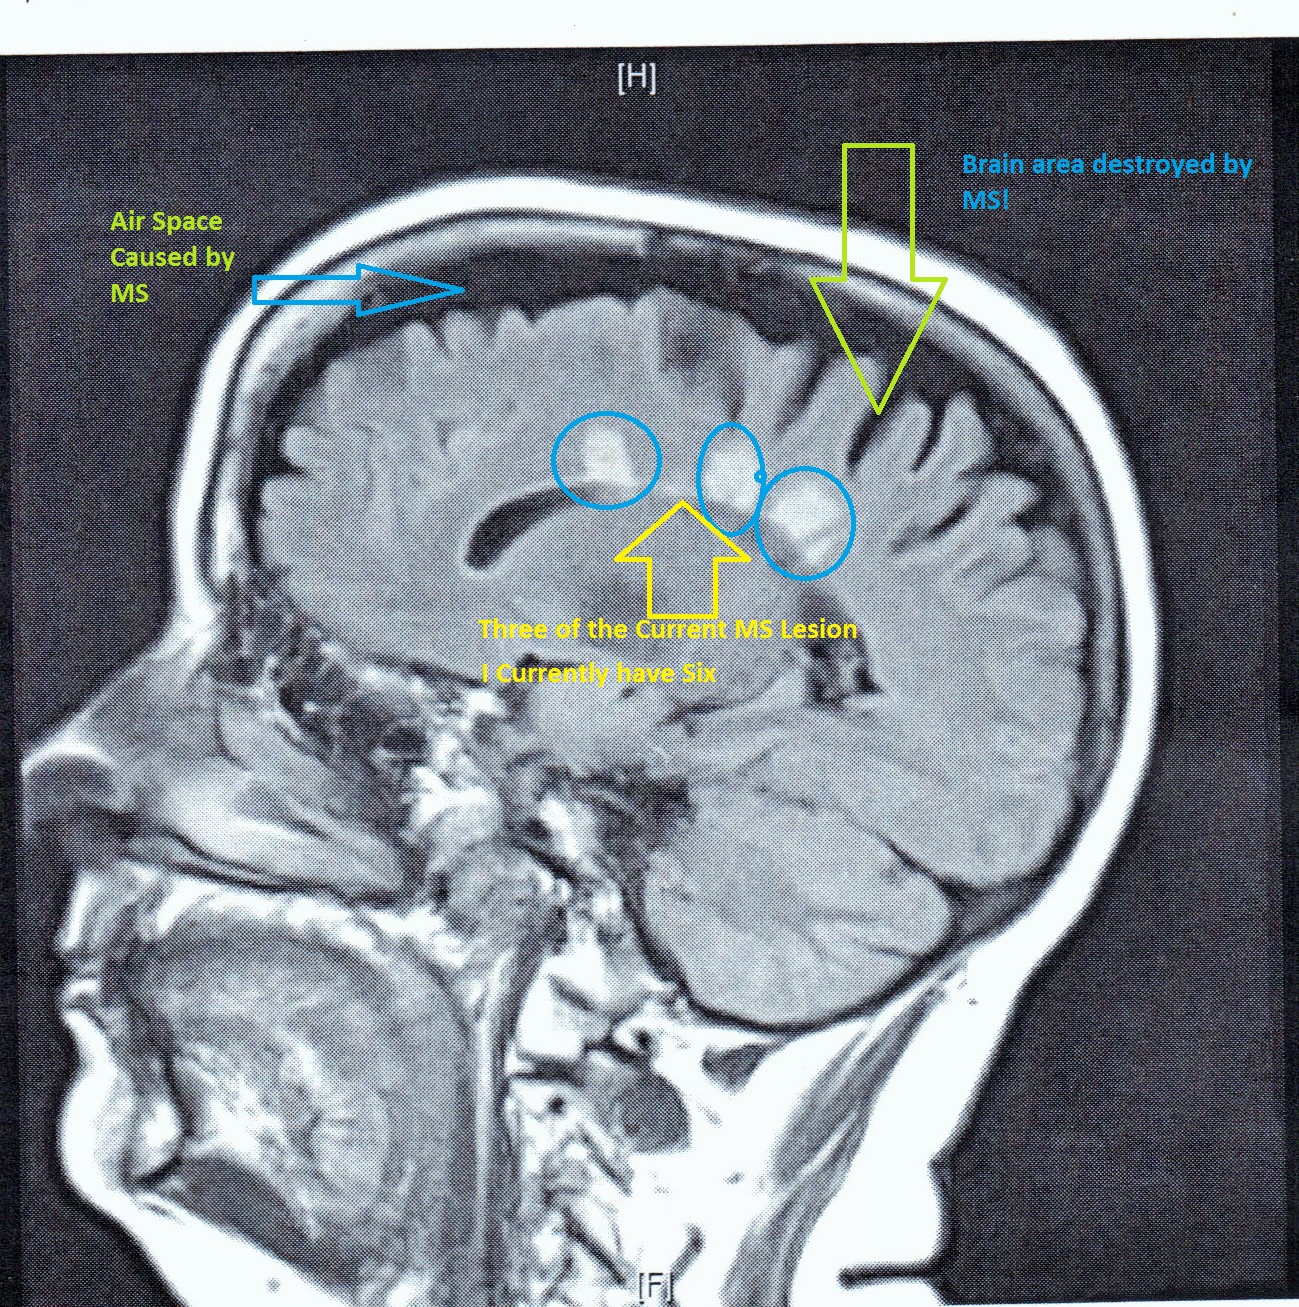

Diana has been on the same medication (Tysabri) for over six years. This is her third MS medication, and the longer a person remains on Tysabri, the greater her chance of developing PML, a deadly brain disease that has no cure. It is for this reason that Diana has sought out stem cell treatment to halt the progression of her condition. The type of stem cell treatment she is seeking does not involve embryonic stem cells. It uses cells from her own body that are re-harvested and infused back and reintroduced for treatment. The stem cells will heal the damage that Multiple Sclerosis process that has damaged Diana’s weakened body.